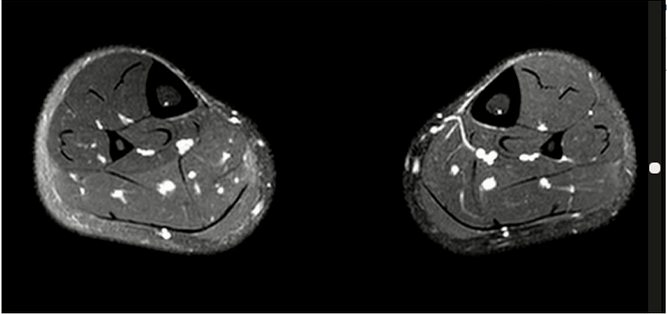

Lisfranc损伤在多发伤病人中常常容易漏诊,大约为 20-30%的漏诊率!